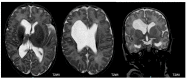

Methods: Very low birth weight (VLBW) infants admitted to the NICU of Modena between 2015 and 2020 were enrolled. Infants who underwent conventional brain magnetic resonance imaging (MRI) at term-equivalent age were included. Neurodevelopmental follow-up was performed until the age of 24 months by a multidisciplinary team using the Amiel-Tison neurological assessment and the Griffiths Mental Developmental Scales (GMDS-R). Neurodevelopmental outcomes were classified as major sequelae (cerebral palsy, DQ ≤ 70, severe sensory impairment), minor sequelae (minor neurological signs such as clumsiness or DQ between 71 and 85), and normal outcomes (no neurological signs and DQ > 85). Risk factors for severe outcomes were assessed.

Results: In total, 49 of the 356 infants (13.8%) died before hospital discharge, and 2 were excluded because of congenital disorders. Of the remaining 305 infants, 222 (72.8%) completed the 24 month follow-up and were included in the study. Neurodevelopmental outcomes were classified as normal (n = 173, 77.9%), minor (n = 34, 15.3%), and major sequelae (n = 15, 6.8%). Among 221 infants undergoing brain MRI, 76 (34.4%) had major lesions (intraventricular hemorrhage, hemorrhagic parenchymal infarction, periventricular leukomalacia, and large cerebellar hemorrhage). In the multivariate regression model, the retinopathy of prematurity (OR 1.8; p value 0.016) and periventricular-intraventricular hemorrhage (OR 5.6; p value < 0.004) were associated with major sequelae.